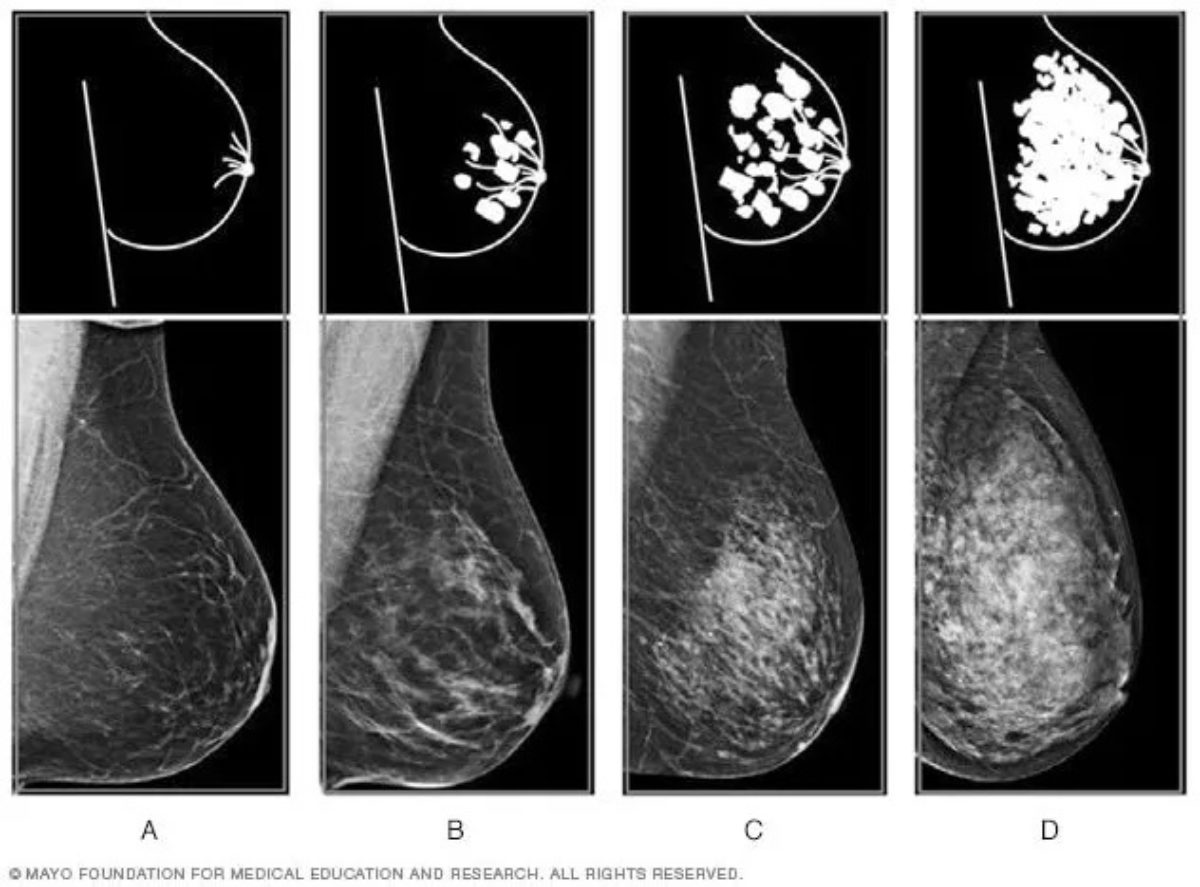

Это наиболее распространенный и доступный способ определения плотности. Маммография позволяет получить рентгеновский снимок молочной железы, по которому врач может оценить уровень плотности. В таблице ниже представлены основные типы плотности, согласно классификации BI-RADS:

| Класс плотности | Описание | Рекомендуемый подход |

|---|---|---|

| A | Молочная железа почти полностью жировая, плотность низкая | Рекомендуется регулярное наблюдение |

| B | Ряд частичных плотных участков, незначительная плотность | Регулярная маммография и осмотры |

| C | Значительные участки плотных тканей, средняя плотность | Дополнительные обследования, МРТ при необходимости |

| D | Высокая плотность, молочная железа почти полностью тканая плотная | Опасно исключать онкологию, контроль у специалиста |

Классификация BI-RADS (Бюро радиологических диагностик Американского колледжа радиологов) помогает систематизировать результаты и определить тактику дальнейших действий. Вот основные категории:

- Класс 1 — Жировая ткань, очень низкая плотность.

- Класс 2 — Ткани с минимальной плотностью, преимущественно жировые.

- Класс 3 — Плотные участки, присутствуют фиброзные ткани.

- Класс 4 — Высокая плотность, значительные участки плотных тканей, возможно наличие подозрительных образований.

Понимание этих категорий помогает женщине лучше ориентироваться в своих результатах и своевременно обращаться к специалистам.